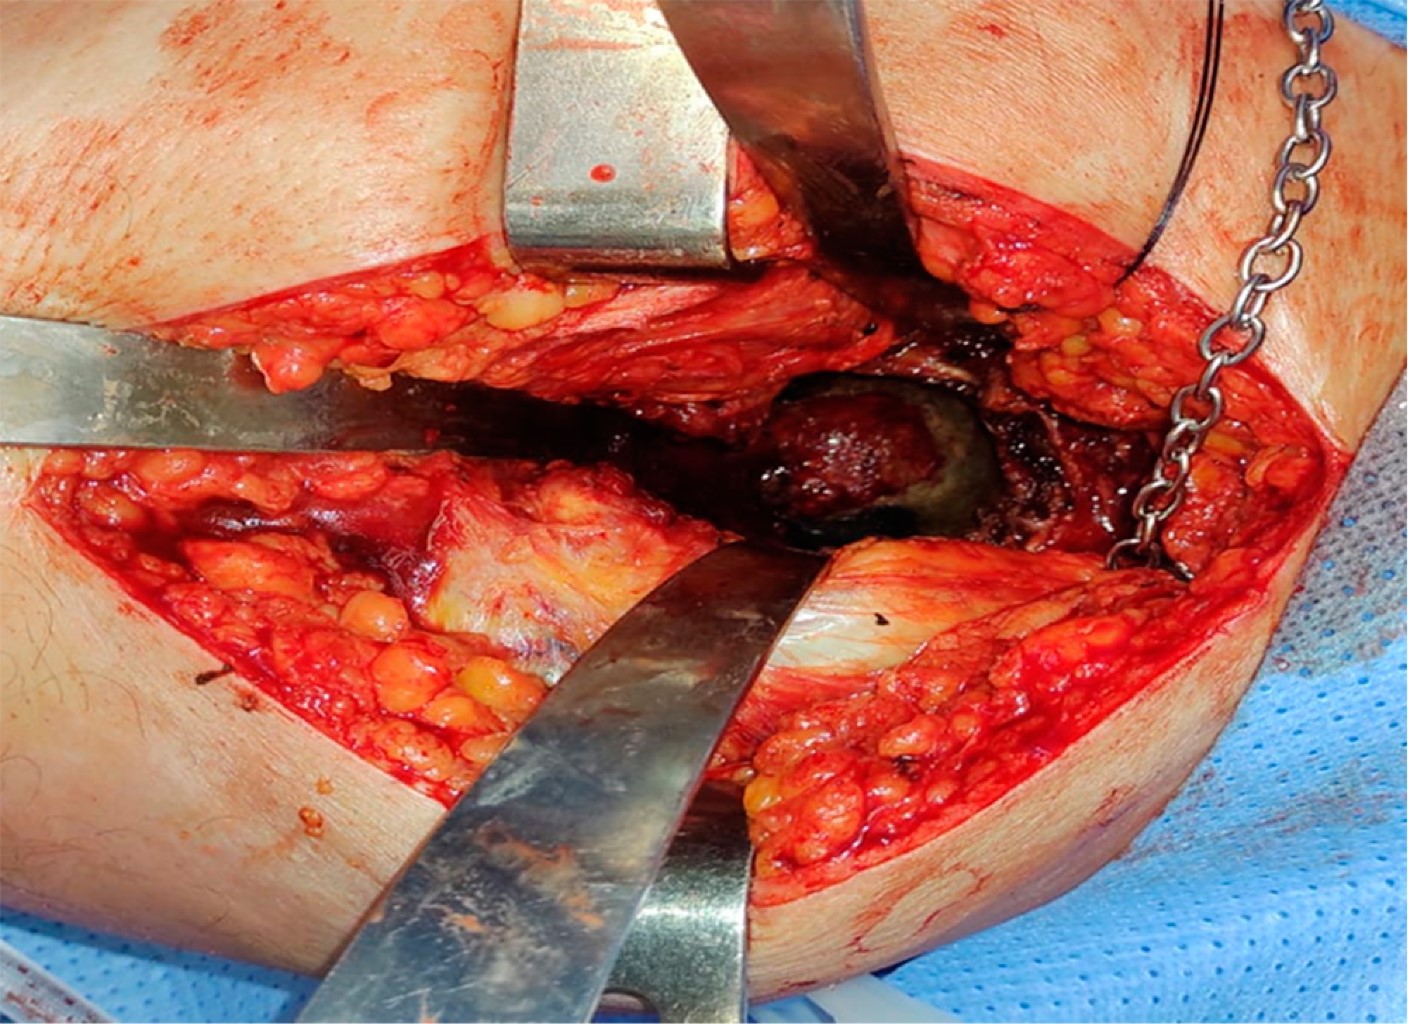

Alkaptonuria: evolution and course of the disease towards ochronotic arthropathy. Series of cases managed with joint replacement

Introduction: alkaptonuria is a very rare metabolic disease with autosomal recessive inheritance due to HGA oxidase deficiency. Classically described and diagnosed in the third to fourth decade of life, affecting both men and women; Its diagnostic impression is clinical based on the blue/black coloration of the conjunctivae, however it is confirmed by the specific analysis of the enzyme in the urine, to date there is no cure and its treatment is palliative and symptomatic. Material and methods: descriptive, observational, case series study, the primary objective of which is to describe the progression of the disease and its involvement in the musculoskeletal system. Results: two clinical cases are presented in women and men in which the broad clinic is illustrated, its progressive advance and the different alterations that it can generate in the musculoskeletal system. Conclusions: alkaptonuria is a rare disease which leads to a severe secondary arthropathy, currently without a specific management which is based on treating the symptoms, in its final stages joint replacements are a management option with satisfactory results for the relief of pain.

Figure 1